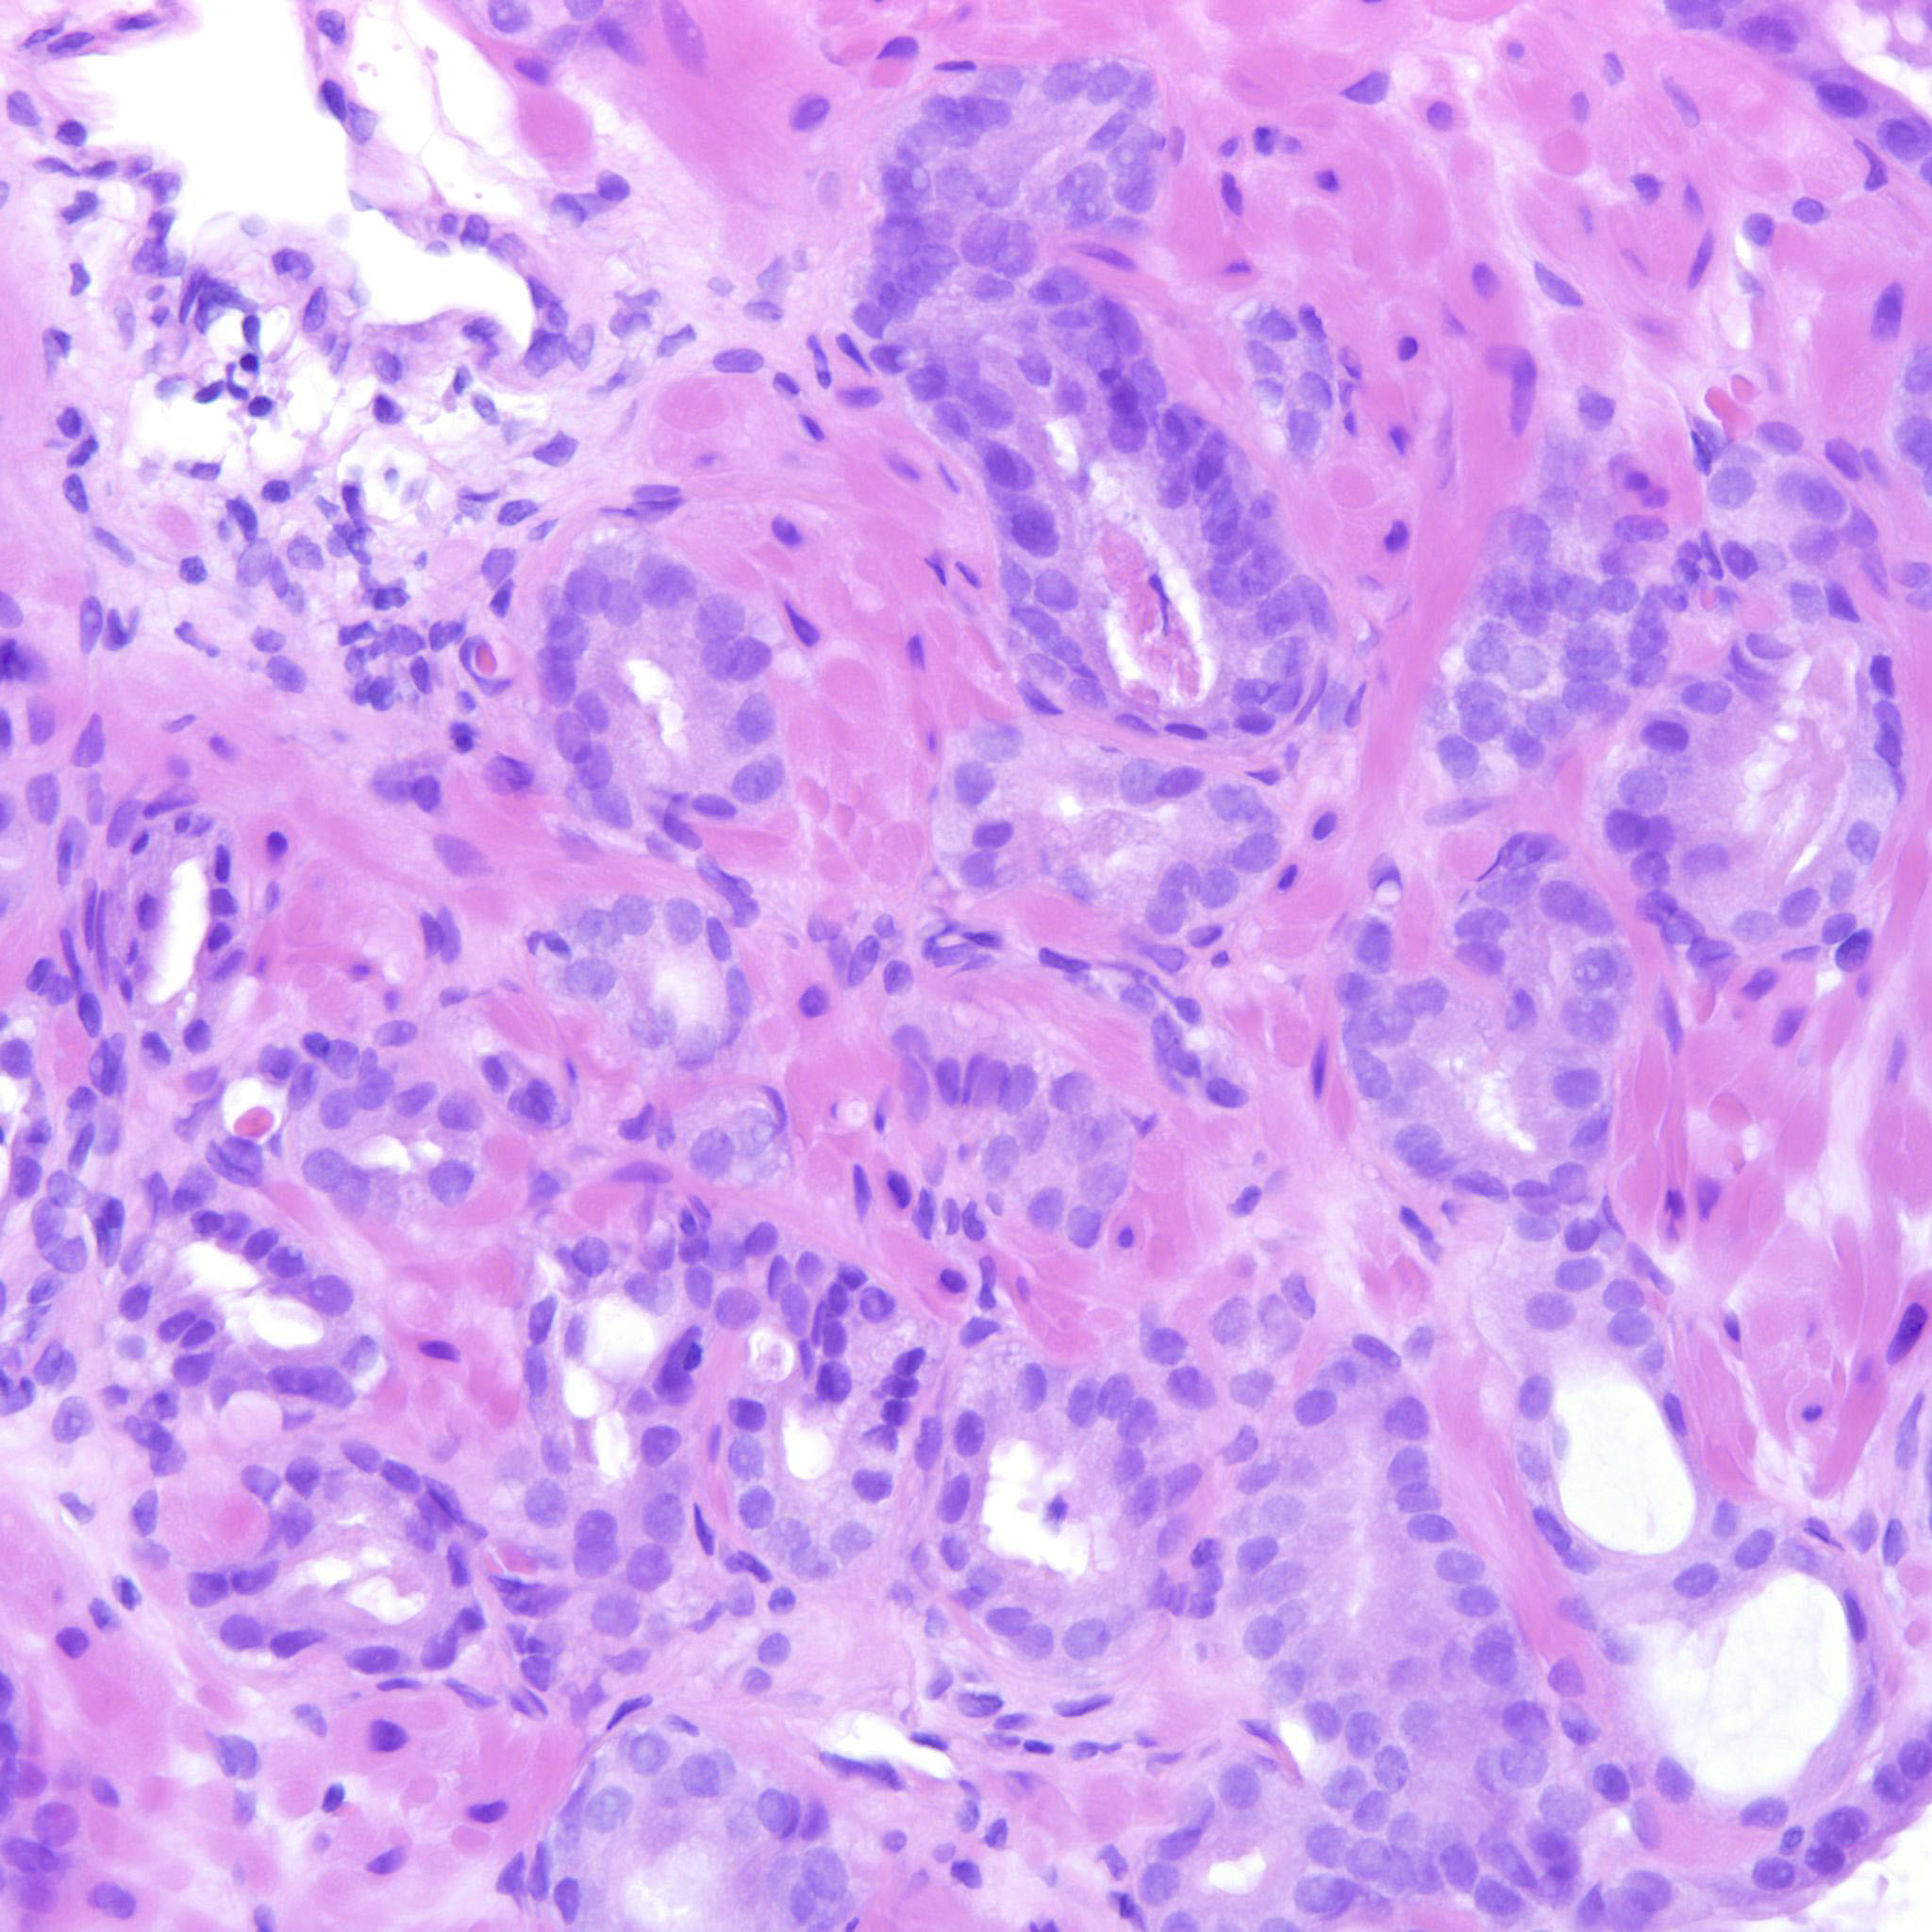

Consensus grade: GS 3+3=6 (ISUP 1)

Case description (by case creator):

3+3=6 bordering towards 3+4. There are rare seemingly poorly formed glands but they can still be overlooked.